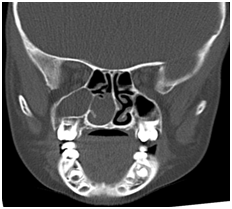

Twenty-one patients (14 male, 7 female, mean age 27.3 ± 16.7, range 7-56) undergoing surgery with a diagnosis of AP in our clinic between September 2012 and January 2015 were examined retrospectively. Detailed history was taken from all patients, and all underwent complete ear, nose and throat examination and nasal endoscopy. Computerized tomography (CT) in the coronal plane was performed on all patients (Figure 1). Endoscopic sinus surgery was performed under general or local anaesthesia. AKP was total excision of the polyp with the antral mucosa (Figure 2). Cases were monitored in terms of postsurgical complications and recurrence.

Figure 1 Computed tomography images, showing features consistent with an antrochoanal polyp.

The most common symptom is unilateral nasal obstruction. Angiofibroma, nasal glioma, inverted papilloma, mucocele mucus retention cyst, meningoencephalocele, Tornwaldt cyst and nasopharyngeal carcinoma must be considered at differential diagnosis of AP.10 There are no marked differences between AP and other polyps in terms of histology. Polyps have a pseudostratified columnar epithelium.11 CT and/or magnetic resonance imaging (MRI) can be used as imaging techniques at diagnosis. APs fill the paranasal sinus at CT and appear as soft tissue masses extending to the central meatus via the ostia and from there to the posterior choana without causing bone destruction. They appear hypointense on T1 images at MR and hyperintense on T2 images.12